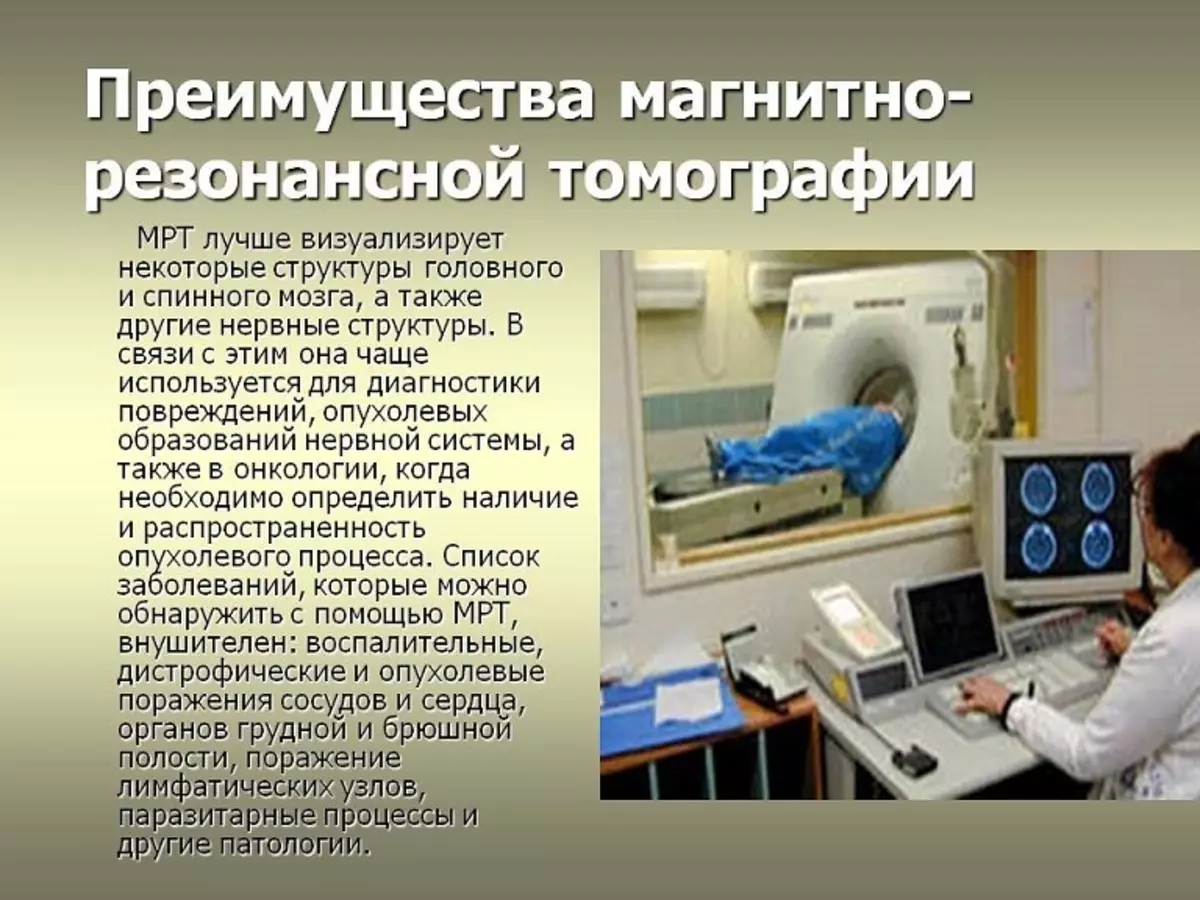

Опухоли головки поджелудочной железы классификация. Доброкачественная опухоль поджелудочной. Доброкачественная опухоль поджелудочной железы. Гистологическая классификация опухолей поджелудочной железы. Магнитно-резонансная томография. Исследования магнитно-резонансной томографии:. Обследование на томографе. Мрт.

Магнитно-резонансная томография. Исследования магнитно-резонансной томографии:. Обследование на томографе. Мрт. Онкологические заболевания. Злокачественная опухоль. Злокачественные новообразования. Опухолевые заболевания.